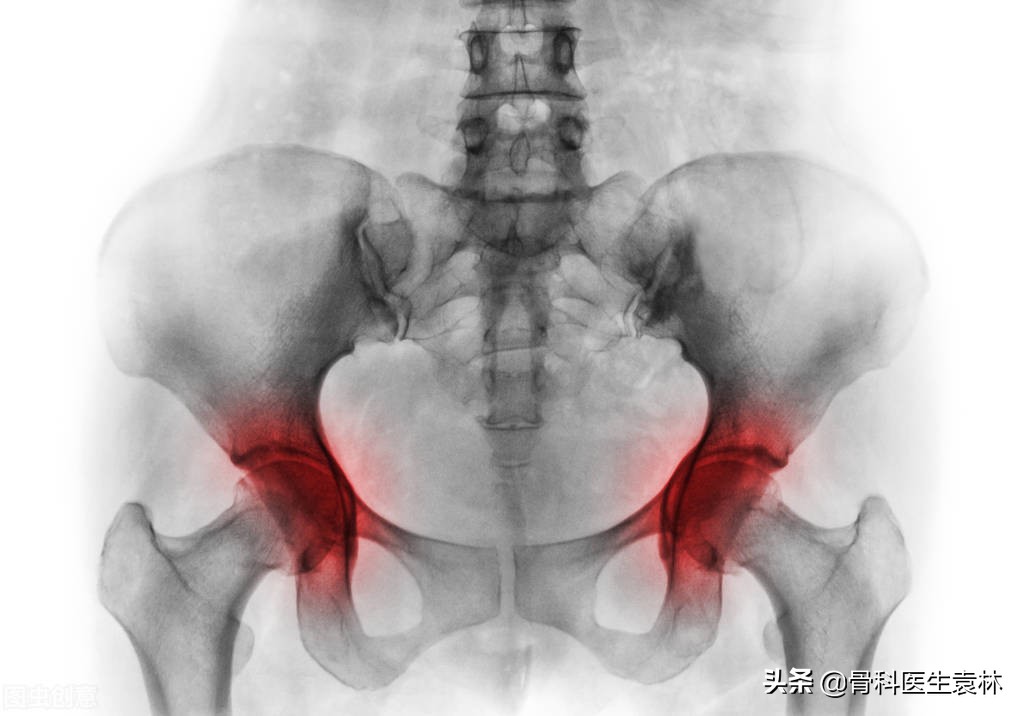

在目前的骨科疾病中,有一种非常常见的疑难病叫做股骨头缺血性坏死,也就是我们常说的股骨头坏死。

这主要是因为外伤、过量饮酒、 服用激素类药物 、 骨质疏松、发育不良以及风湿病等因素所引起的。

股骨头坏死症状表现有哪些?

一般都是由间断性的疼痛发展到持续性的疼痛,进而引发人体肌肉的痉挛以及活动受限制,甚至是致残或跛行。